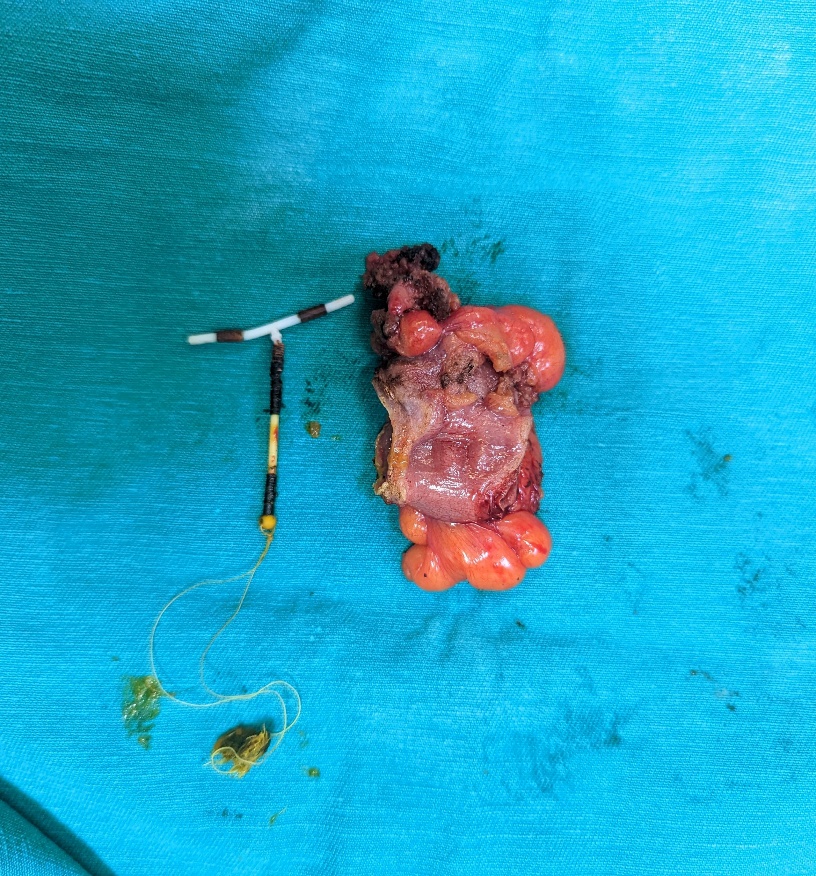

Trong quá trình tiến hành ca mổ nội soi, đoạn đại tràng sigma bị dụng cụ tử cung xuyên thủng được cắt bỏ, 2 đầu đại tràng được nối lại cũng qua nội soi nên vết mổ chỉ khoảng 3cm đủ để lấy bệnh phẩm ra ngoài. Ngay ngày đầu tiên sau mổ, bệnh nhân được ăn cháo và tập đứng dậy, vận động đi lại. Bệnh nhân được xuất viện sau 6 ngày.

Dụng cụ tử cung và đoạn đại tràng được lấy ra sau mổ, vết mổ khoảng 3cm